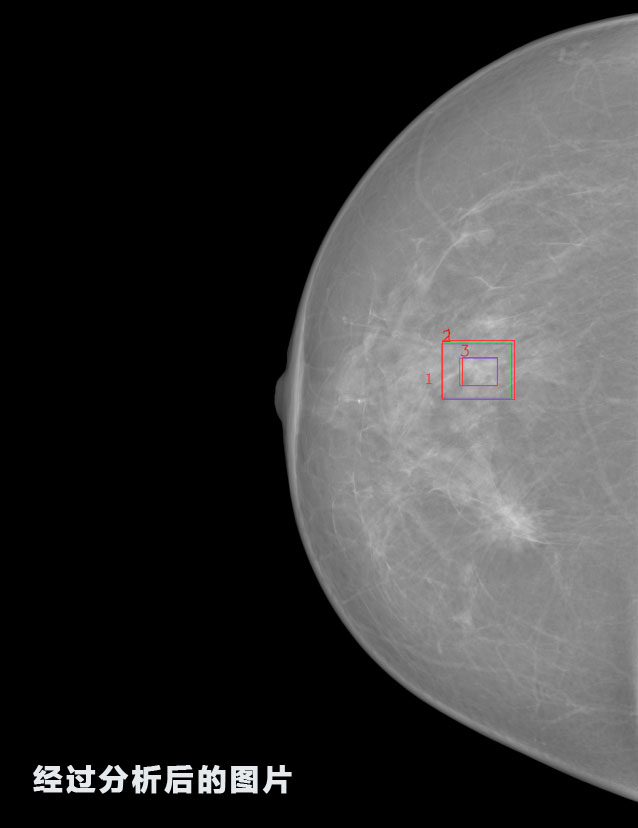

1.發現良性鈣化,可能性為19.88%---位置框指數:[1796.0867 1359.8237 2058.1372 1582.5334]

2.發現惡意鈣化的可能性為15.18%---位置框指數:[1789.4733 1365.9951 2063.7698 1576.0613]

3.發現惡意鈣化的可能性為12.45%---位于框指數:[1859.3987 1422.3184 2006.5494 1528.2698]